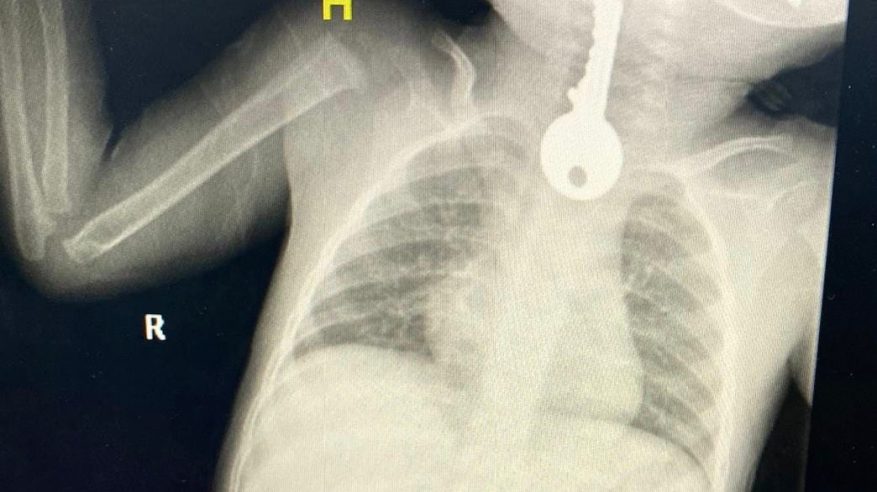

تمكن فريق طبي في محافظة الطائف من إنقاذ طفل كاد أن يفارق الحياة بعد أن أُحضِر إلى قسم الطوارئ في حالة حرجة وتم إجراء عملية له بالمنظار تكللت ولله الحمد بالنجاح.

وبين مجمع الملك فيصل الطبي أنهم استقبلوا حالة طفل في وضع صحي حرج يعاني من ضيق في التنفس، مما استدعى تقديم الإسعافات الأولية وإجراء الفحوصات السريرية والإشعاعية التي كشفت وجود جسم غريب على شكل مفتاح في المريء.

وأوضح الفريق المعالج للحالة أنه تم على الفور عمل منظار عاجل واستخراج مفتاح حديدي من المريء كاد أن يودي بحياته ثم متابعته في قسم التنويم من قبل الفرق التمريضية حتى استقرت الحالة وخرج بالسلامة ولله الحمد.